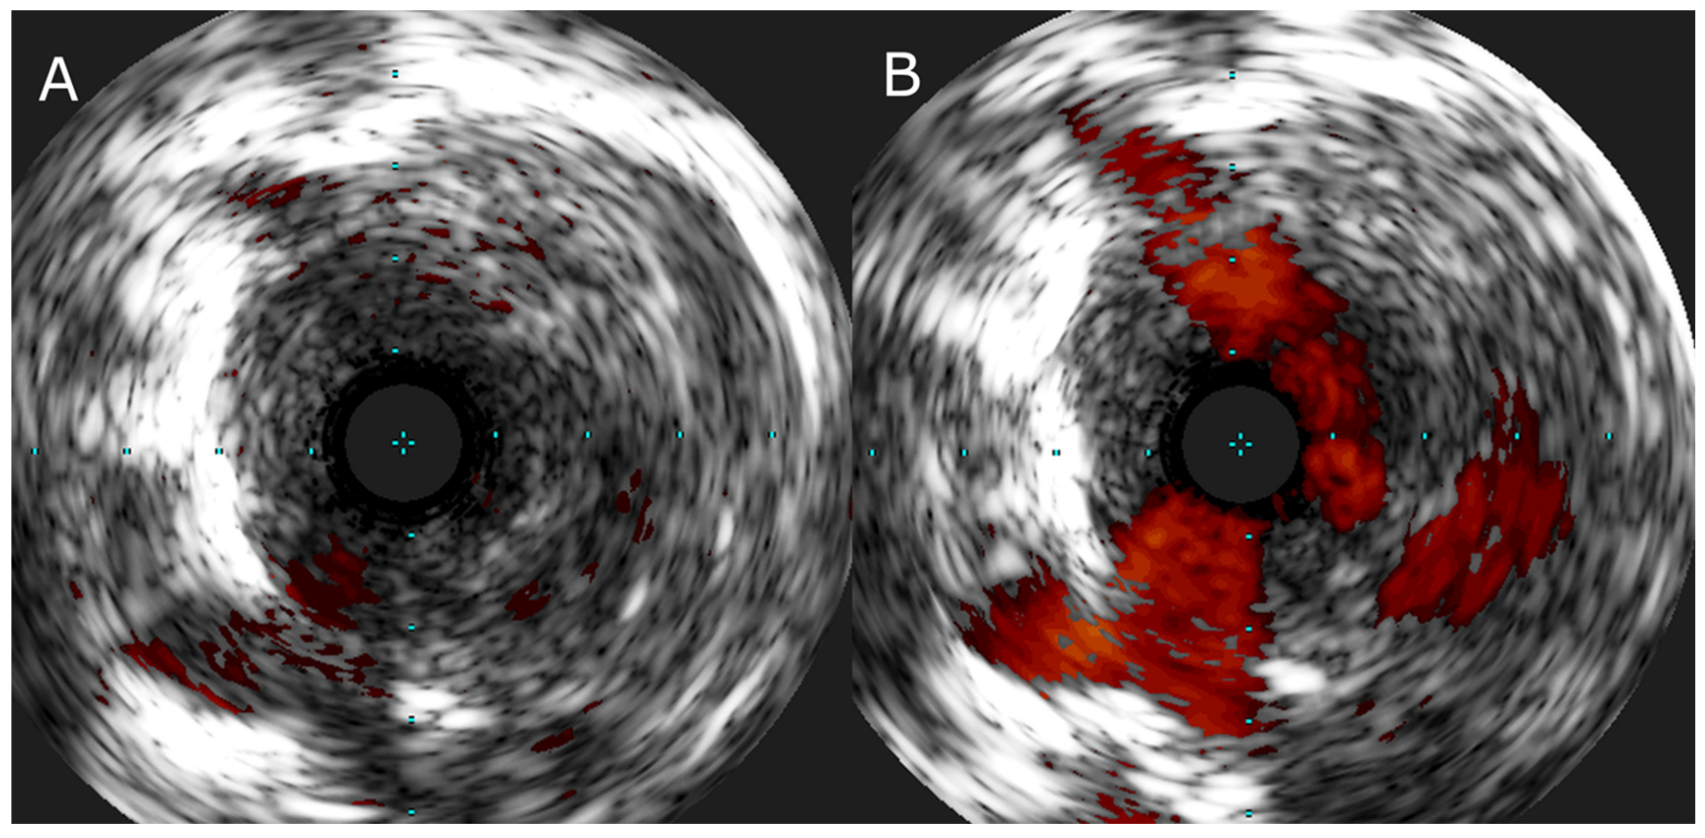

- Araszkiewicz, A.; Jankiewicz, S.; Łanocha, M.; Janus, M.; Mularek-Kubzdela, T.; Lesiak, M. Optical coherence tomography improves the results of balloon pulmonary angioplasty in inoperable chronic thrombo-embolic pulmonary hypertension. Postępy Kardiol. Interwencyjnej 2017, 13, 180–181. [Google Scholar] [CrossRef]